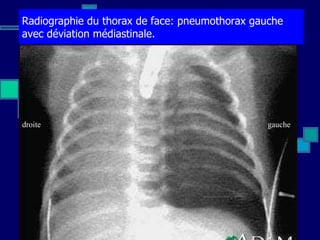

![Détresses respiratoires: Autres causes liées à l’appareil respiratoire - Infection à suspecter dans tous les cas de détresse respiratoire - Hernie diaphragmatique et autres malformations (atrésie des choanes, trachéomalacie, syndrome de Pierre Robin [micro rétrognatisme, fente palatine, glossoptose], malformation kystique adénomatoïde congénitale pulmonaire,….) - O bstructions des voies aériennes, ….](https://image.slidesharecdn.com/coursauxesfde3ilunga2011octobre-111126042619-phpapp01/85/Cours-aux-esf-de-3-ilunga2011-octobre-22-320.jpg)